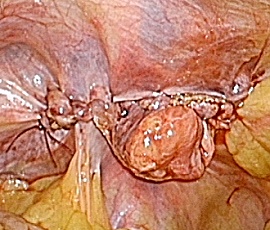

検診にて左下腹部の腫脹を指摘され受診。精査の結果、鼡径ヘルニア嵌頓(かんとん)と診断。手術(腹腔鏡下ヘルニア手術(TAPP法))を施行した。

手術画像